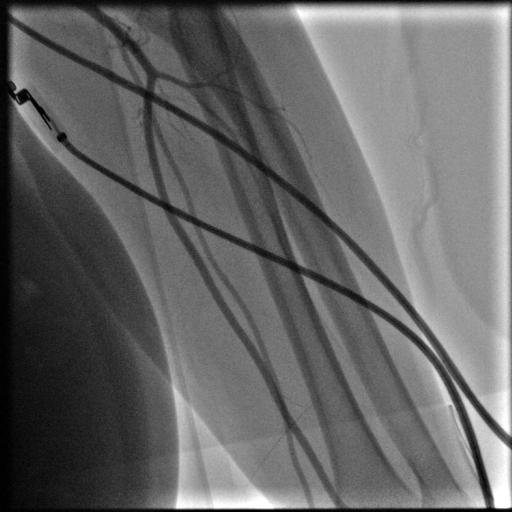

Yürürken bacak ağrısı olan ve ayak parmaklarında iyileşmeyen yaraları olan hastanın yapılan tetkiklerinde bacak damarlarının diz üstü ve diz altı tıkalı olduğu tespit edildi.Anjio da balon ve stent işlemiyle damarları açıldı. Hastamız şu an sağlıklı bir şekilde hayatına devam etmektedir.